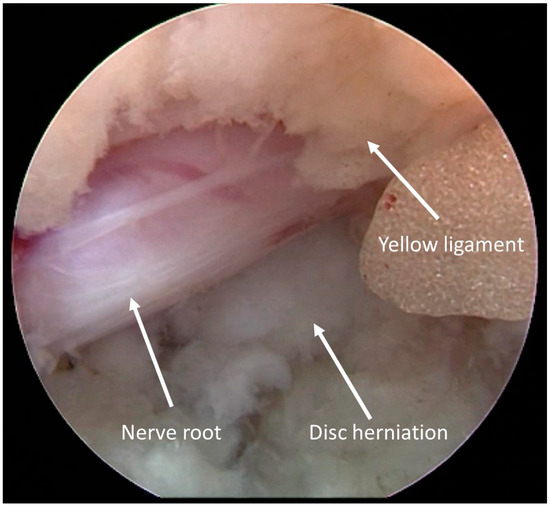

3.3. Clinical Case 1